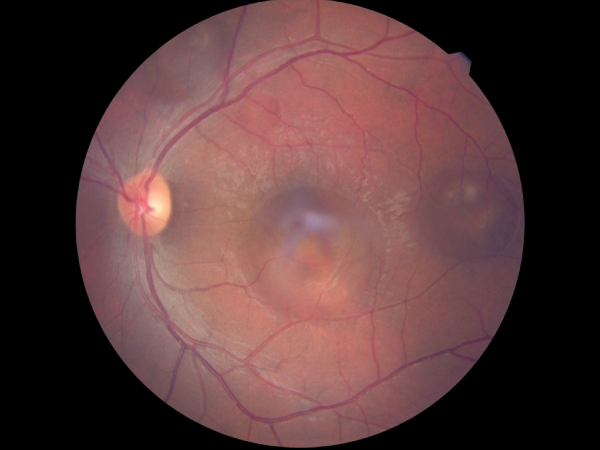

Branch retinal vein occlusion with collaterals and macular edema

BRVO post sectorial laser photocoagulation